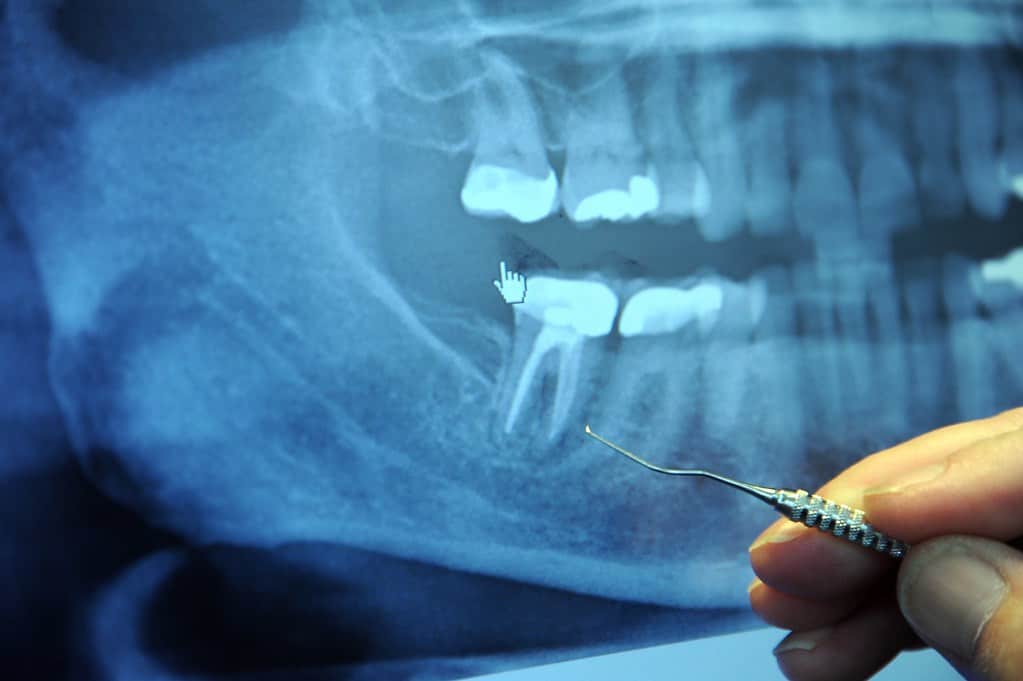

जबड़े में फ्रैक्चर का निदान करने के लिए डॉक्टर शारीरिक परिक्षण और एक्स-रे करता है। जबड़े के लिए पैनोरैमिक एक्स-रे बेस्ट होता है।आमतौर पर ब्लड टेस्ट की जरूरत नहीं पड़ती है। डॉक्टर आपके TMJ जॉइंट्स चेहरे की विकृति, सूजन, चोट के निशान आदि की जांच करता है। इसके बाद डॉक्टर मुंह के अंदर जांच करता है, आपको कुछ काटने, दांतों को एक-दूसरे पर बिठाने के लिए कहता है।